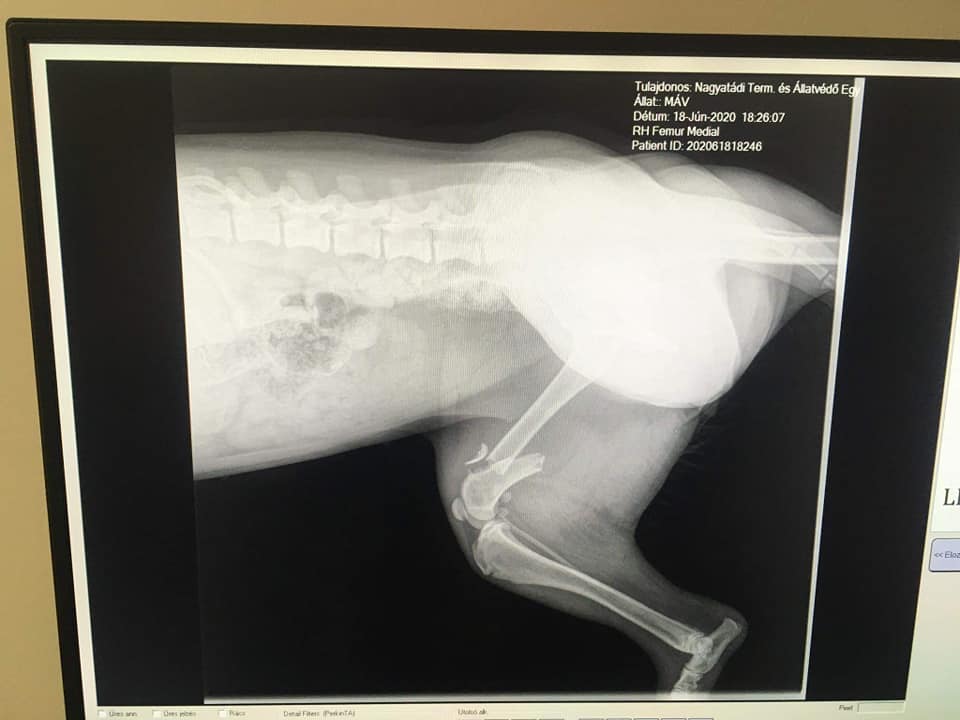

Eine weitere sehr traurige Nachricht erreichte uns aus Ungarn. (Nagyatád) Vor 2 Tagen wurde die kleine Máv von einem Zug erfasst. Ihr wurden dadurch beide Beine gebrochen. Die junge Hündin lag 2 Tage zwischen den Gleisen, man dachte, sie sei tod.

Doch Máv lebte, schwer verletzt und mit grossen Schmerzen. Sie musste so schlimme Ängste aushalten! Täglich rauschten mehrere Züge an ihr vorbei und sie konnte sich selber nicht davon bewegen. Sie ist nun in unserer Obhut und einige Operationen werden nötig sein, um die kleine Seele zu retten.